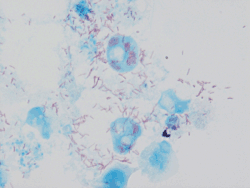

"Rickettsia conorii" observed in Vero cells (red rods; magnification ×1,000)

Rickettsia conorii observed in Vero cells (red rods; magnification ×1,000)[1]